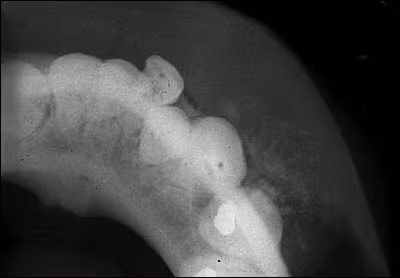

Radiographic Findings The periapical radiograph demonstrated a well-defined mixed radiolucent/radiopaque lesion that caused divergence of the roots without resorption. An occlusal radiograph also revealed buccal expansion and scattered opacifications (Figures 2 and 3).

Figure 3. Mandibular occlusal radiograph demonstrating the mixed radiolucent/radiopaque nature of this lesion.